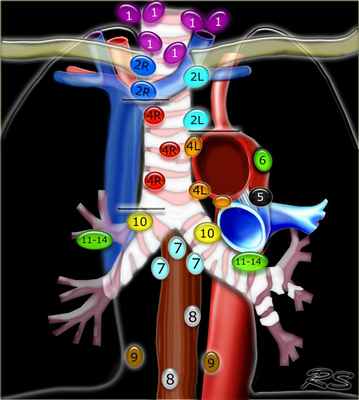

Это обновление статьи 2007, в которой для стадирования рака легких (MD-ATS карты) использовалось деление регионарных лимфатических узлов по Mountain-Dresler (1).

С целью согласования различий используемых в классификациях Naruke и MD-ATS, в 2009 году Международная ассоциация по изучению рака легкого (IASLC) предложила классификацию регионарных лимфатических узлов.

В этой статье представлены иллюстрации и КТ-изображения для лучшего понимания этой классификации.

Классификация регионарных лимфатических узлов IASLC 2009 г.

Надключичные лимфатические узлы

1 Нижние шейные, надключичные и лимфатические узлы вырезки грудины (левые и правые).

Располагаются по обе стороны от срединной линии трахеи в нижней трети шеи и надключичных областях, верхней границей является нижний край перстневидного хряща, нижней - ключицы и яремная вырезка рукоятки грудины .

Верхние медиастинальные лимфатические узлы 2-4

2L Левые верхние паратрахеальные располагаются вдоль левой стенки трахеи, от верхнего края рукоятки грудины до верхнего края дуги аорты.

2R Правые верхние паратрахеальные располагаются вдоль правой стенки трахеи и спереди от трахеи до ее левой стенки, с уровня верхнего края рукоятки грудины до нижней стенки левой плечеголовной вены в зоне пересечения с трахеей.

3А Преваскулярные лимфатические узлы не примыкают к трахее как узлы 2 группы, а располагаются кпереди от сосудов (от задней стенки грудины, до передней стенки верхней полой вены справа и передней стенки левой сонной артерии слева)

3P Превертебральные(Ретротрахеальные) располагаются в заднем средостении, не примыкают к трахее как узлы 2 группы, а локализуются кзади от пищевода.

4R Нижние паратрахеальные от пересечения нижнего края плечеголовной вены с трахеей до нижней границы непарной вены, вдоль правой стенки трахеи до ее левой стенки.

4L Нижние паратрахеальные от верхнего края дуги аорты до верхнего края левой главной легочной артерии

Аортальные лимфатические узлы 5-6

5. Субаортальные лимфатические узлы располагаются в аортопульмонарном окне, латеральнее артериальной связки, они расположены не между аортой и легочным стволом, а латеральнее них.

6. Парааортальные лимфатические узлы лежат спереди и сбоку от восходящей части дуги аорты

Нижние медиастинальные лимфатические узлы 7-9

7. Подкаринальные лимфатические узлы.

8. Параэзофагеальные лимфатические узлы. Лимфатические узлы ниже уровня карины.

9. Узлы легочной связки. Лежат в пределах легочной связки.

Корневые, долевые и (суб) сегментарные лимфатические узлы 10-14

Все эти группы относятся к N1 лимфатическим узлам.

Узлы корня легкого располагаются вдоль главного бронха и сосудов корня легкого. Справа они распространяются от нижнего края непарной вены до области деления на долевые бронхи, слева – от верхнего края легочной артерии.